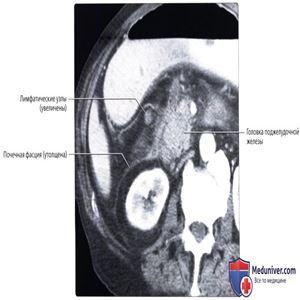

Нисходящий отдел двенадцатиперстной кишки всегда расположен чуть латеральнее головки поджелудочной железы. Наблюдается спадение просвета двенадцатиперстной кишкии инфильтрация прилегающих забрюшинных межфасциальных плоскостей и пространств. Увеличение прилегающих лимфатических узлов обусловлено воспалением (реактивная гиперплазия). В последствии подтверждена прободная язва. Воспаление поджелудочной железы или двенадцатиперстной кишки приводит к инфильтрации переднего параренального пространства и утолщению около почечной фасции, образующей заднюю стенку этого пространства.